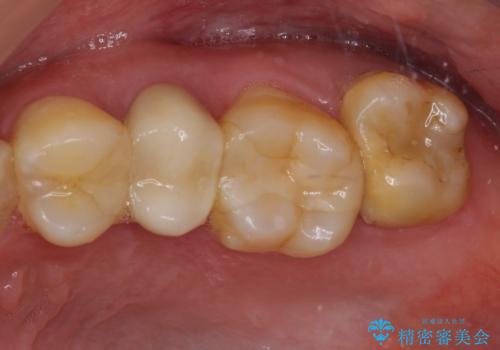

冷たいものがしみて奥歯が痛い 気になる歯並びも治した